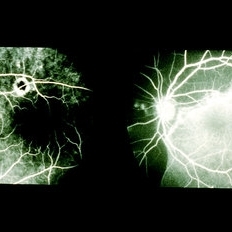

Massive Vitreous Hemorrhage 1

Mar 14 2013 by Maurice F. Rabb

This 59 year-old black female was referred with marked decrease in vision in the right eye. She had massive sub-RPE and subretinal hemorrhage. This went on to massive vitreous hemorrhage.

Condition/keywords: decrease in vision, retinal pigment epithelium, subretinal hemorrhage

Massive Vitreous Hemorrhage 2